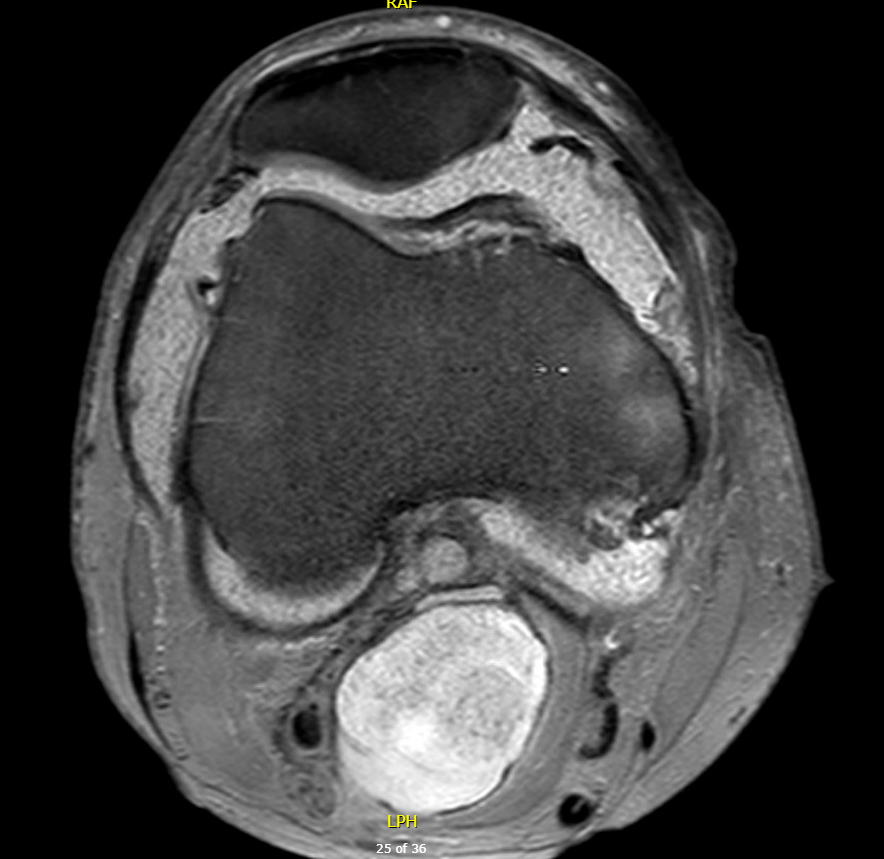

MRI

Synovial Proliferation

Soft tissue lesions same signal intensity as cartilage

Synovial chondromatosis

Synovial osteochondromatosis